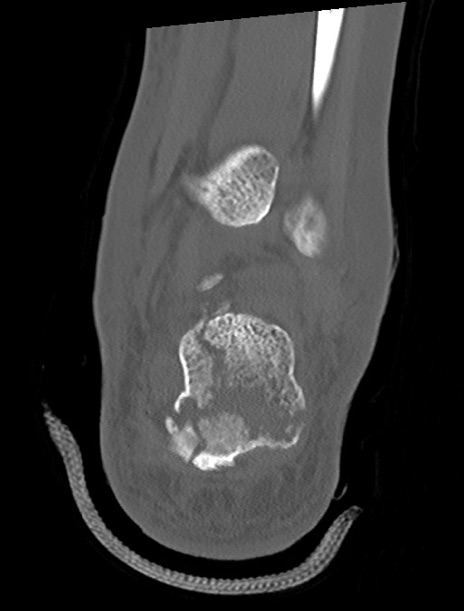

左足関節CT

3D再構成